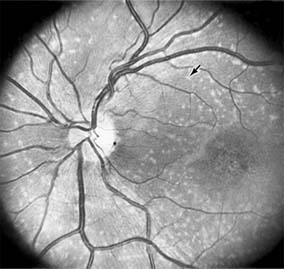

Nonexudative age-related macular degeneration is characterized by variable degrees of atrophy and degeneration of the outer retina, retinal pigment epithelium, Bruch's membrane and choriocapillaris. Of the ophthalmoscopically visible changes in the retinal pigment epithelium and Bruch's membrane, drusen are the most typical (Figure 10-1). Drusen are discrete, round, yellow-white deposits of variable size beneath the pigment epithelium and are scattered throughout the macula and posterior pole. With time, they may enlarge, coalesce, calcify, and increase in number. Histopathologically, most drusen consist of focal collections of eosinophilic material lying between the pigment epithelium and Bruch's membrane; they therefore represent focal detachment of the pigment epithelium. In addition to drusen, clumps of pigment irregularly dispersed within depigmented areas of atrophy may progressively appear throughout the macula. The level of associated visual impairment is variable and may be minimal. Fluorescein angiography demonstrates irregular patterns of retinal pigment epithelial hyperplasia and atrophy. Electrophysiologic testing in most patients is normal.

Figure 10-1

Figure 10-1: Age-related macular degeneration with discrete (small arrow) and large confluent (large arrow) macular drusen.